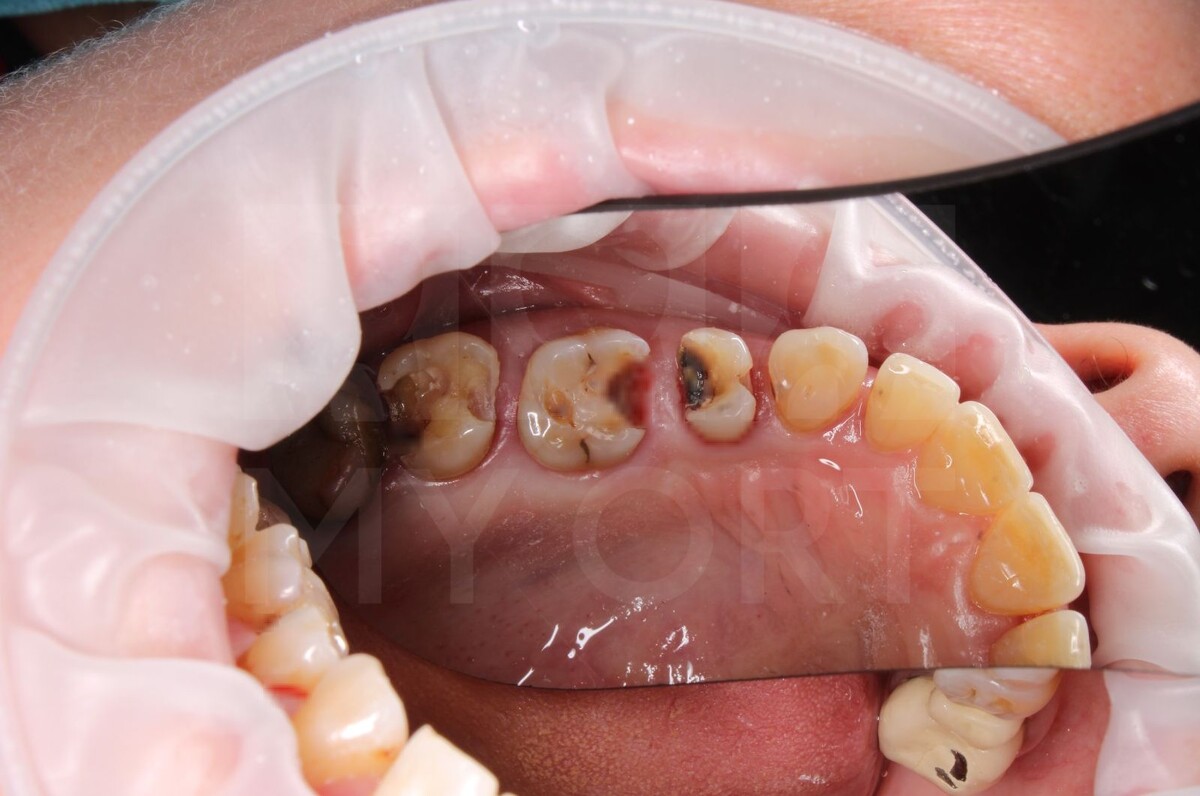

Пациентка из Ленинградской области, обратилась ко мне с жалобами на отсутствие зубов, старые коронки, дискомфорт в виде болевой реакции на холодное и горячее, застревание пищи в кариозных полостях и на неприятный запах. У неё наблюдались отсутствующие зубы, старые коронки, которые уже отходили и было значительное разрушение зубов.

До моего посещения пациентке уже удалили достаточно много зубов и поставили небольшой протез.